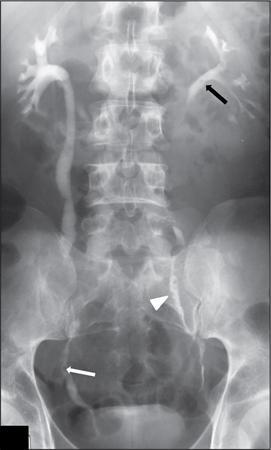

Uretritis cystica (Fig. 10.14.3)

Ureteritis cystica results in multiple filling defects which may also be seen in a multifocal UCC. The ureter is not obstructed hence not dilated.

Image

Fig. 10.14.3 IVP image showing pyeloureteritis cystica: Multiple smooth oval to round lucent filling defects are seen in both ureters (white arrow and arrowhead) and in left renal pelvis (black arrow). (Source: Courtesy of Dr. Mukund Rahalkar.)

In polyureteritis cystica, multiple small cysts are seen in the ureteric wall. These are seen as multiple small filling defects in the proximal ureter; however, the fluid containing cysts are too small to sample and obtain density measurements. The filling defects are more numerous than those in multifocal urothelial carcinoma.